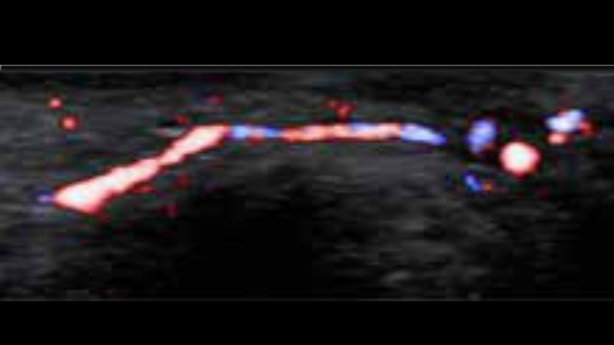

System ultrasonograficzny Zeus jest wyposa?ony w?przyjazny interfejs u?ytkownika i??atwe w?u?yciu funkcje umo?liwiaj?ce skuteczne skanowanie. Jego wszechstronne funkcje obejmuj? ultrasonografi? jamy brzusznej, naczyniow?, ma?ych narz?d├│w i?uk?adu mi??niowo-szkieletowego, zwi?kszaj?c pewno?? diagnostyczn?.